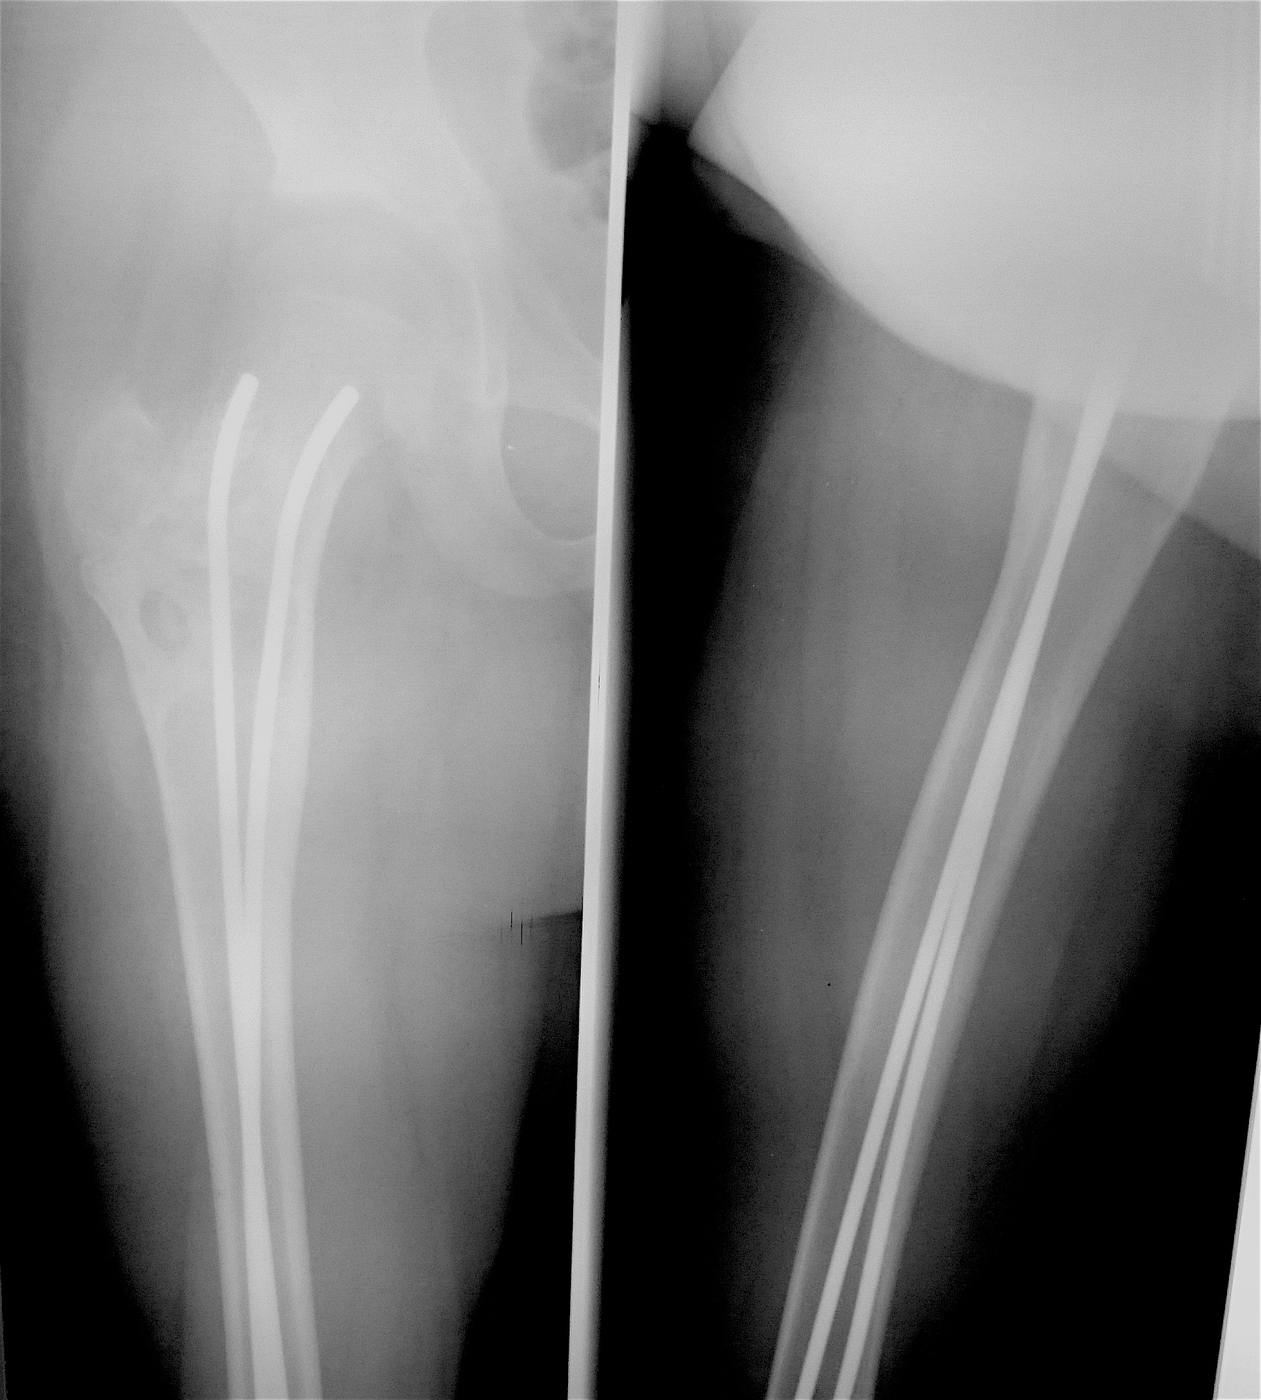

Закрытый, паталогический перелом в подвертельной области правой бедренной кости со смещением, на фоне аневризмальной костной кисты.

Выполнена резекция с аллопластикой губчатыми и кортикальными биоимплантатами "Лиопласт".